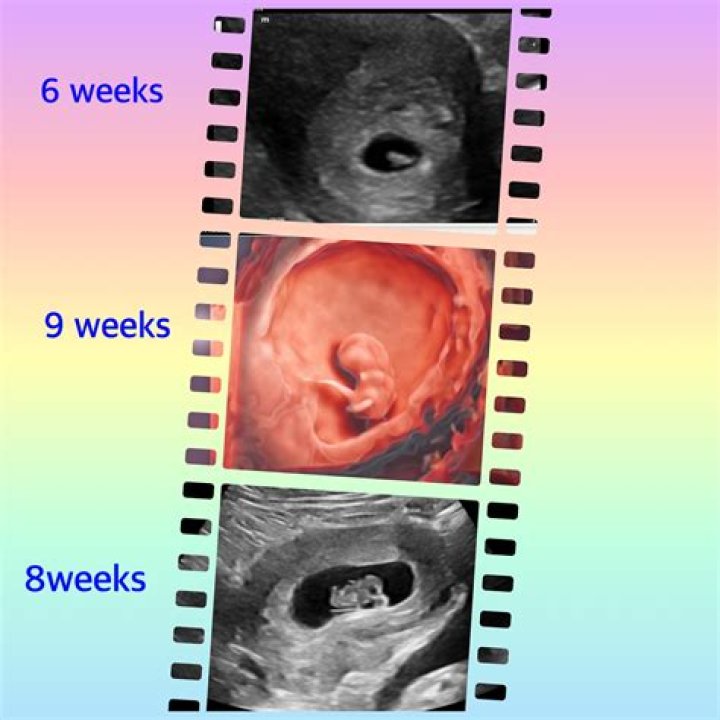

How soon should you see an OB-GYN when pregnant?